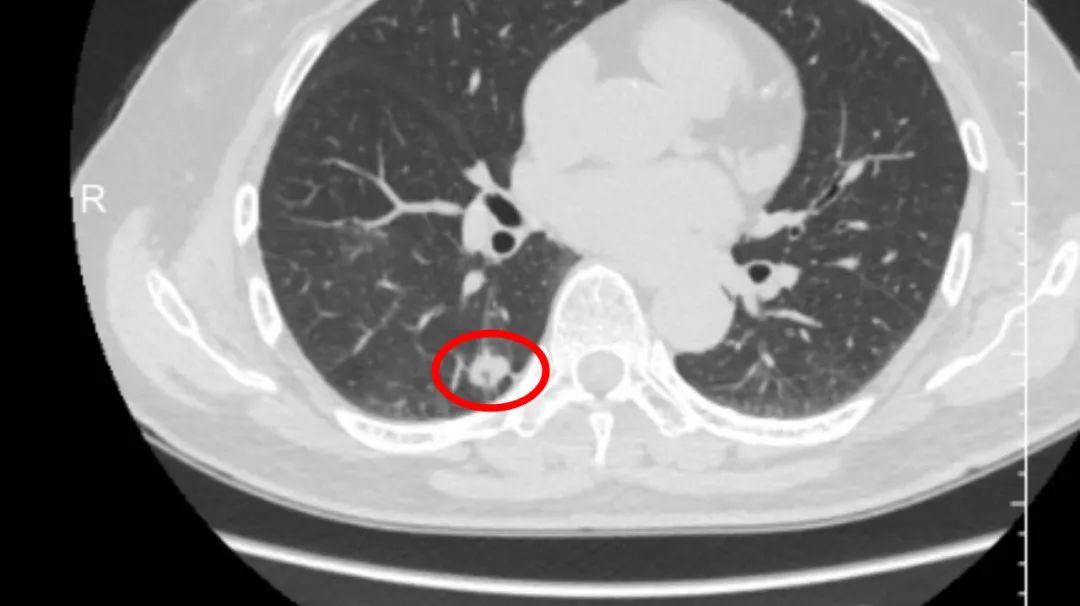

在胸外科病房就诊的张大爷,今年75岁,因健康查体胸部CT发现“右肺下叶高危结节”。经综合检查评估后,考虑右肺恶性肿瘤可能性大。

入院后,为保证完整切除病灶的同时,最大程度保留正常肺组织,胸外科主治医师孙彬科学制定了吲哚菁绿荧光单孔胸腔镜下右肺下叶后基底段切除术方案。术中,在荧光模式下,可以清楚的显示切除边界,手术顺利完成,术中快速病理为“浸润性腺癌”。目前,患者正有序康复中。